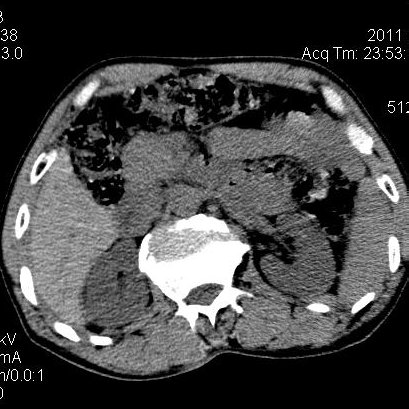

肝左叶发育异常

男性,55岁,骑摩托车摔倒后入院,自述右上腹疼痛

[backcolor=#FF0000]第一次诊断的时候也是这么肯定,可是床旁超声检查并没有发现明显异常,而且患者的一般症状都良好。还好临床只是保守治疗,没有立即手术,第二次复查的时候没有一点变化,又做了MRI检查,没有血肿,

这是一例肝左叶发育异常的,很个性吧~[/backcolor]